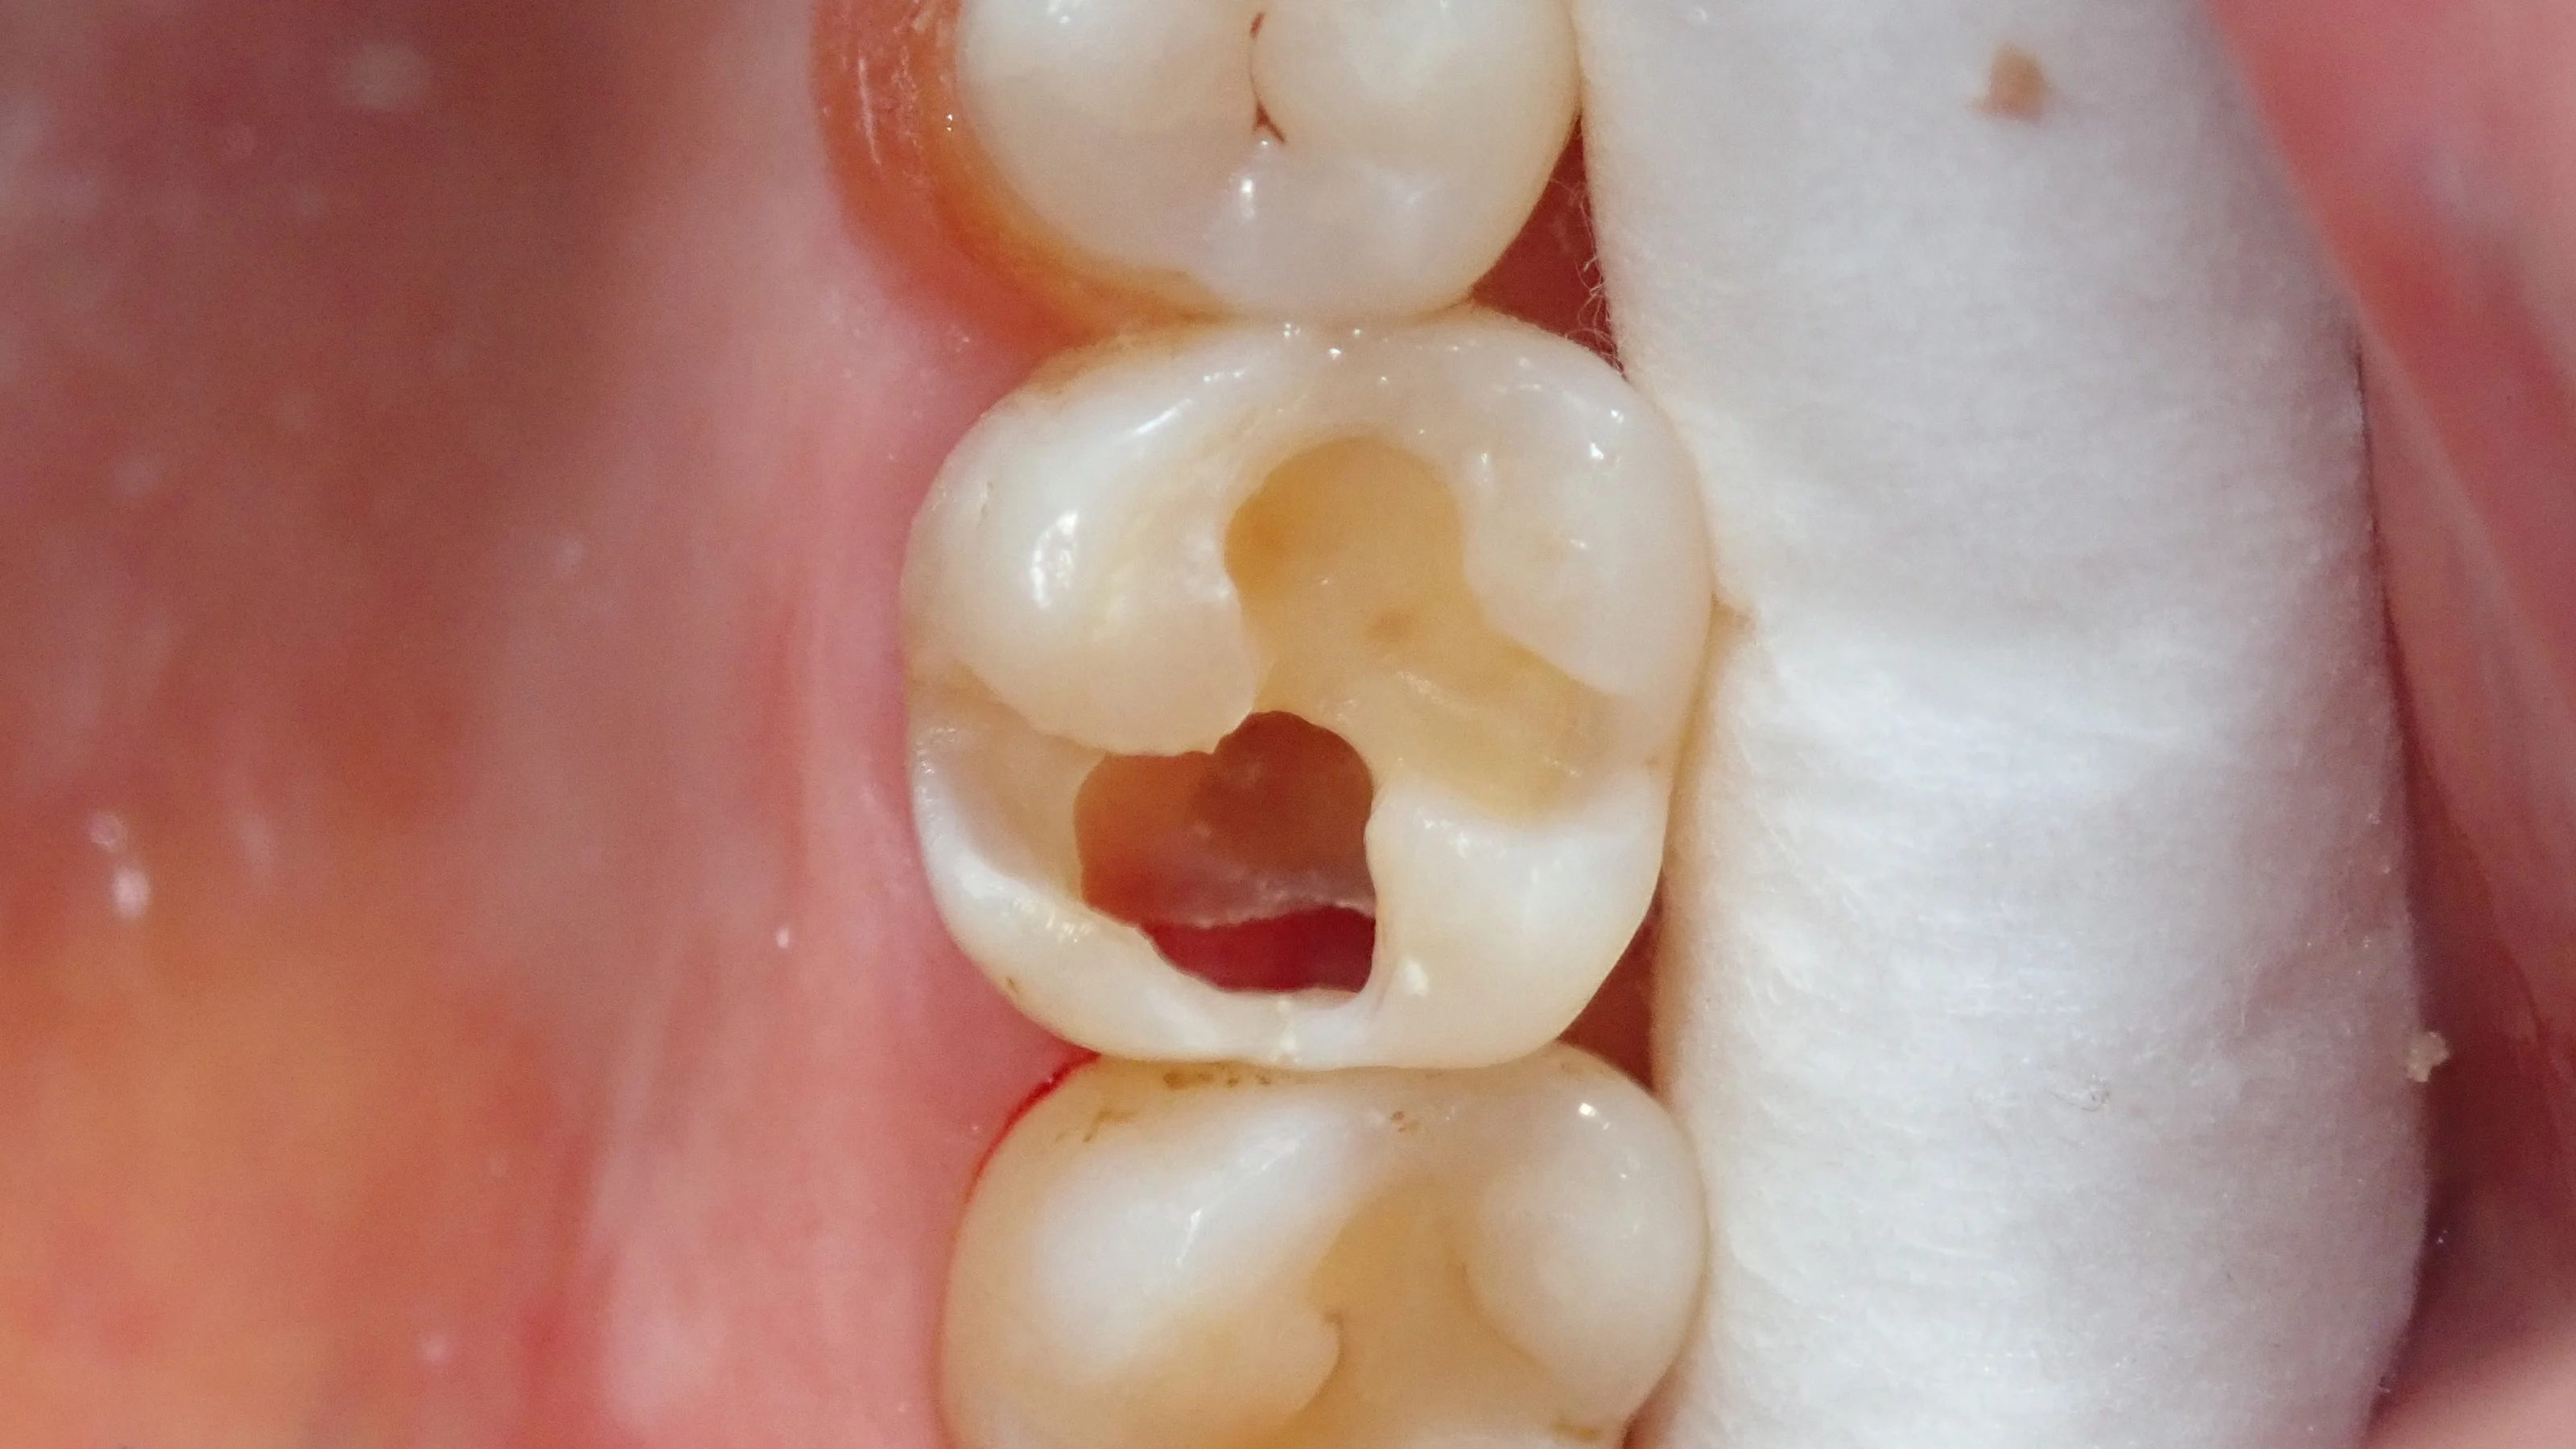

そういえば、坂寄歯科医院で現在実際に行っているダイレクトボンディング(臼歯)の症例写真を載せていなかったなと思いましたので、載せていきたいと思います。

ひとまず、いつも通り

術前です。

白い部分は仮封材 (いわゆる仮の蓋)が入っており、虫歯は既に取り切っている状況です。

私はよく「虫歯だけ取って、次回最終的なものの型取り・詰める」といった処置をします。

専門用語だと「覆罩」と呼ばれる処置です。

理由としては

・一気に型取りまで行って、もし痛みが出たりすると困る

・深い虫歯であれば連続で処置するよりも一度神経を休憩させてから処置した方が、神経を取らずに済むことが多い

・結果として歯を残せる

・複数歯の治療をまとめてやる時は、覆罩→型取り→Setとした方が来院回数が少なくて済む

・・・などです。

今回の場合は1本だけですが、あまりに虫歯が大きく深かったため、覆罩を行いました。